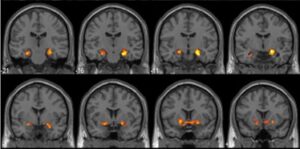

استخدم هذا البحث التعاوني أحدث تقنيات التصوير بالرنين المغناطيسي الوظيفي (fMRI) لتسجيل أنماط نشاط الدماغ وعمله الجاد أثناء انخراط المشاركين في فهم صور غامضة يصعب فهمها في البداية.

الحُصين، منطقة دماغية عميقة معروفة بدورها المحوري في التعلم وترسيخ الذاكرة. لاحظ الباحثون أنه عندما يمر الناس بلحظات الكشف يصبح الحُصين فجأة أكثر نشاطًا من الناحية العصبية، حيث تُثير هذه اللحظات نشاطًا عصبيًا.

لم يكتفِ الباحثون بدراسة مناطق الدماغ العميقة، بل درسوا أيضًا القشرة القذالية الصدغية البطنية. هذه المنطقة متخصصة في التعرّف على الأشكال والأشياء والأنماط البصرية.

وجد الباحثون قرائن على أنه بمجرد أن يمر المشاركون بلحظة الكشف، تتغير أنماط التنشيط العصبي في هذه المنطقة لتعكس “تفسيرًا” جديدًا للمثيرات البصرية. ببساطة، يُعيد الدماغ تنظيم كيف يدرك الصورة ويمثلها ذهنيًا عندما يجد الحل. وعندما يُدرك الدماغ الحل فجأةً، يبدأ برؤية الصورة بشكل مختلف. فهو لا يفهم الإجابة فحسب، بل يُعيد تنظيم طريقة تمثيل الصورة ذهنيًا، مُنشئًا طريقة جديدة لرؤية الشيء لم تكن موجودة من قبل.

والأهم من ذلك، تداخلت هذه التأثيرات مع زيادة في الاتصالية بين منطقة الحُصين (الذي يساعد على تكوين الذاكرة) والقشرة القذالية الصدغية البطنية (التي تساعد على إدراك ما يراه المرء).

وأبرزت الدراسة أنه خلال لحظة الكشف، تتواصل هاتان المنطقتان الدماغيتان المختلفتان بشكل أكثر قوة وكفاءة، مُشكلةً شبكة ديناميكية تدمج ترميز الذاكرة [تحويل المعلومات الحسية إلى شكل يمكن تخزينه في الذاكرة واستعادته لاحقًا] مع إعادة التفسير الإدراكي. وهي اللحظة التي يُحدّث فيها الدماغ فهمه للشيء، ويتغير إدراك المرء ليتوافق مع المعنى الجديد، أي رؤية الشيء بطريقة جديدة أو مختلفة بعد تغيير المرء فهمه.